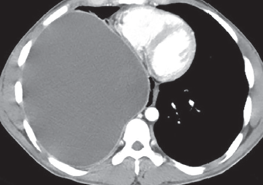

Vishesh Kumar, MD; Neeraj Saini, MD; Vivek Saini, MD

A 55-year-old female with history of triple negative breast cancer stage IIA status presents with pleuritic right-sided pain in the infrascapular region with progressive dyspnea on exertion over the past 2...